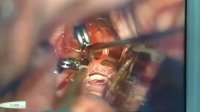

عمل آنوریسم مغزی

دکتر مهرداد حسین زاده بختوری

جراحی آنوریسم مغزی در آقای جوان به دنبال خونریزی و هماتوم مغزی

دکتر گیو شریفی (جراح مغزو اعصاب و ستون فقرات )

فیلم واقعی جراحی تومور بزرگ مغزی یک خانم 64 ساله

دکتر محمودرضا عباس زاده